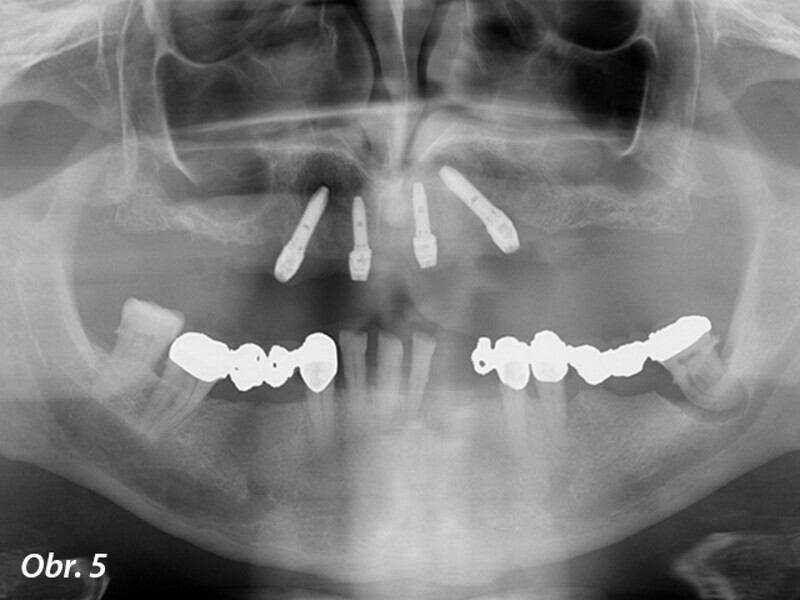

Kouzelné „ALL ON FOUR“